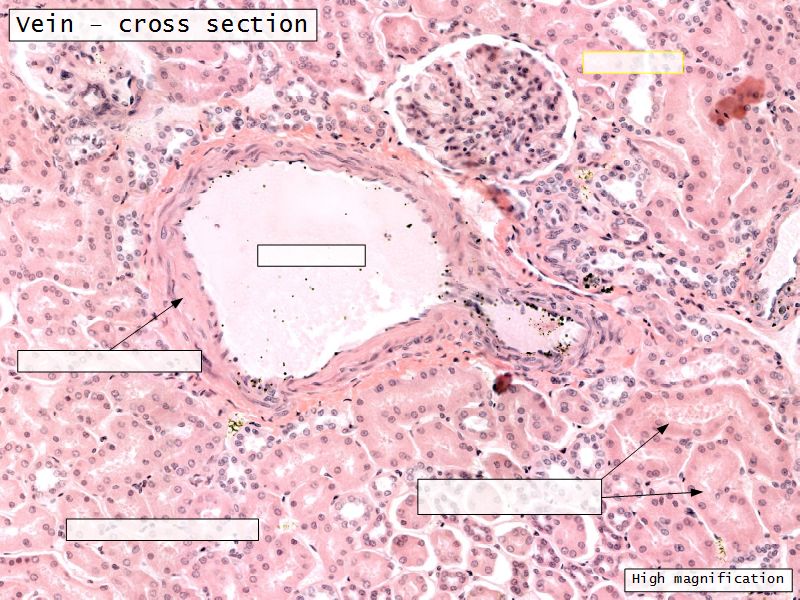

Blood flow

- Efferent arteriole

- Smooth muscle in media

- Capillaries

- Fenestrated

- Afferent arteriole

- Smooth muscle in media

Epithelium layers

- Capillary endothelium

- Visceral layer of epithelium

- Podocytes

- Resting on glomerular basement membrane

- Capsular space

- Parietal layer of epithelium

- Simple squamous epithelium

Capillaries

- Supported by

- Mesangial cells

- Mesangial matrix

- Phagocytic

- Maintain basement membrane

- Remove macromolecular deposits

Mesangial cells

- Around capillary loops at vascular pole

- Phagocytic

- Maintain basement membrane

- Remove macromolecular deposits